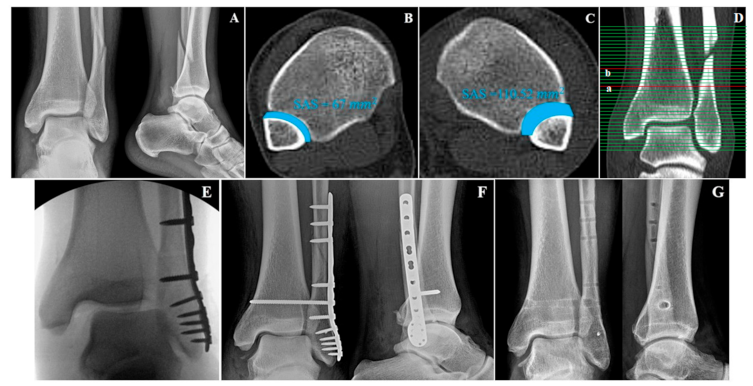

Figure 1).

The study also utilized a new parameter to evaluate syndesmotic injuries. The surface area of syndesmosis (SAS) was measured 1.0 cm and 1.5 cm above the tibial plafond. From here, the researchers named them SAS 1.0 and SAS 1.5, respectively. The method for measurements of SAS 1.0 and SAS 1.5 was established by a consultative meeting made up of specialist in ankle joint trauma (SWL, CHP, BSK). The inferior border of the tibial plafond was first identified on the axial section and cross-referenced with the coronal section with scout imaging using CT scan. Each parameter (SAS 1.0 and SAS 1.5) was measured in the axial section of CT scan, which corresponds with the coronal section 1.0 cm and 1.5 cm above the tibial plafond (

Figure 2). If there is a fracture line in the area to be measured at fibular site, that area was included as fracture diastasis.